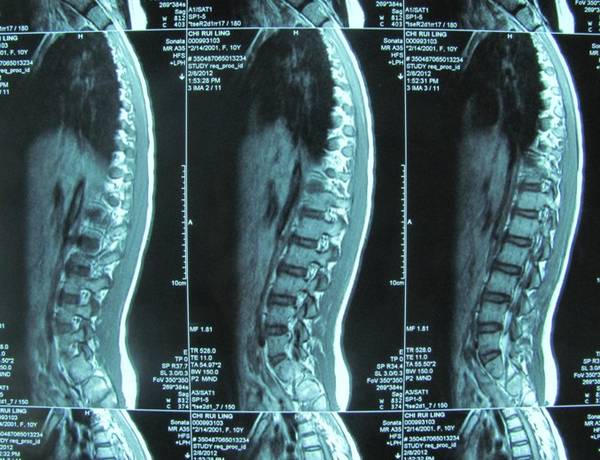

共同讨论一个病例:

半年前患儿洗脚时无意中发现右足踇趾不能伸直,后此症状无变化。

查体:右踇趾下垂,屈曲位不能伸直,被动伸直可,右踇趾感觉正常。右足2-4趾背伸力量减弱,右足2-4趾短伸肌肌腹处未触及肌肉主动收缩。左足伸踇趾及其他足趾伸趾力量减弱。

左踇趾肌力0级

2-5趾4级

右踇趾肌力3级

2-5趾5级弱

小儿神经科会诊,未明确诊断